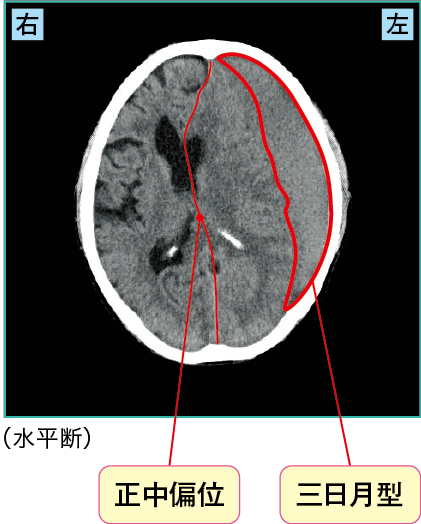

2)急性硬膜下血腫

急性硬膜下血腫は、頭部外傷により脳の表面にある動脈が破れて出血し、硬膜とくも膜の間に血腫ができたものです(図3)。

図3 急性硬膜下血腫

頭部CT画像では、脳表を覆うように三日月型の高吸収域が見られるのが特徴です。また、硬膜とくも膜の結合は弱く血腫が拡がりやすいため、血腫が大きいと脳が圧迫され、正中偏位(midline shift〈ミッドラインシフト〉)が見られることがあります。

出血源は脳表動脈が多く、ほかにも架橋静脈の損傷等でも、急性硬膜下血腫が生じやすいとされます。

損傷部位により頭蓋内圧亢進症状(頭痛 ・悪心 ・ 嘔吐)や脳損傷による麻痺感覚障害などさまざまな症状がみられます。重篤である場合は、脳ヘルニア症状(瞳孔不同異常肢位異常呼吸など)が見られます。

また、脳自体が損傷している場合(脳挫傷)も多いため、受傷直後から意識清明期がなく意識障害が重度である場合が多いとされています。

図3の症例では血腫により頭蓋内圧が亢進し、頭痛・嘔吐が出現していました。